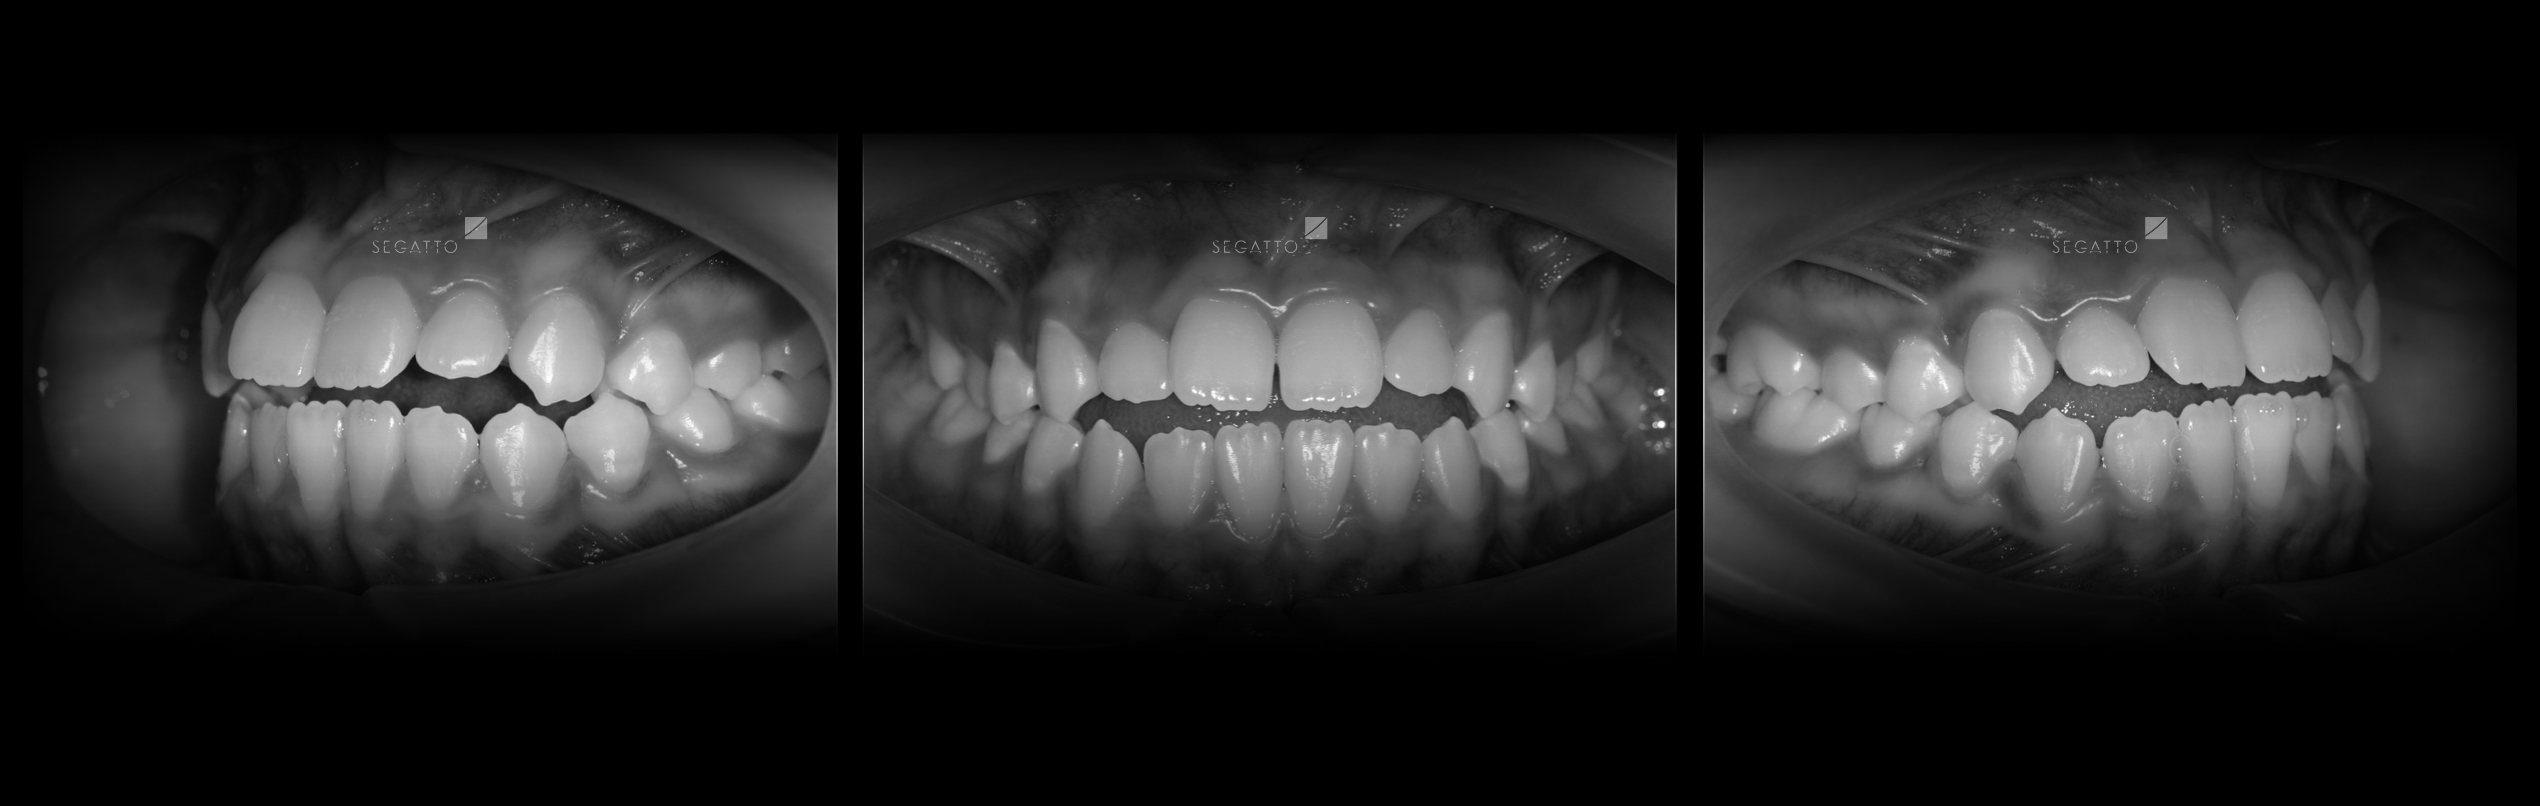

Orthodontics

Cases